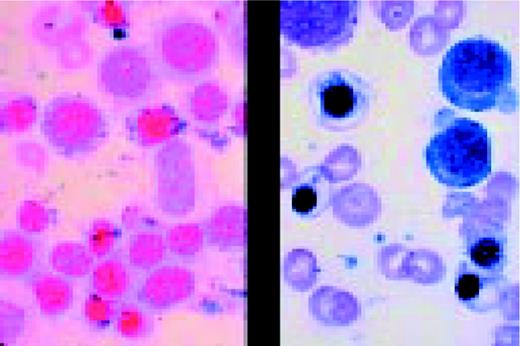

Prolymphocytic leukemia (PLL). This composite slide shows prolymphocytic leukemia (PLL) from two different patients. On the left is B cell PLL and on the right, T cell PLL. The B-PLL cells correspond to the classic description of Galton et al. (Br J Haematol 27:7, 1974): They are larger than CLL lymphocytes, have condensed chromatin, and have prominent large nucleoli. The T-PLL cells have a less conspicuous nucleolus, an irregular nuclear outline, and cytoplasmic blebs, as described by Matutes et al. (Blood 78:12, 1991). In many cases it may (FIX) be difficult to distinguish B-PLL from T-PLL cells on morphologic grounds alone, without performing additional immunophenotypic studies.FIG14